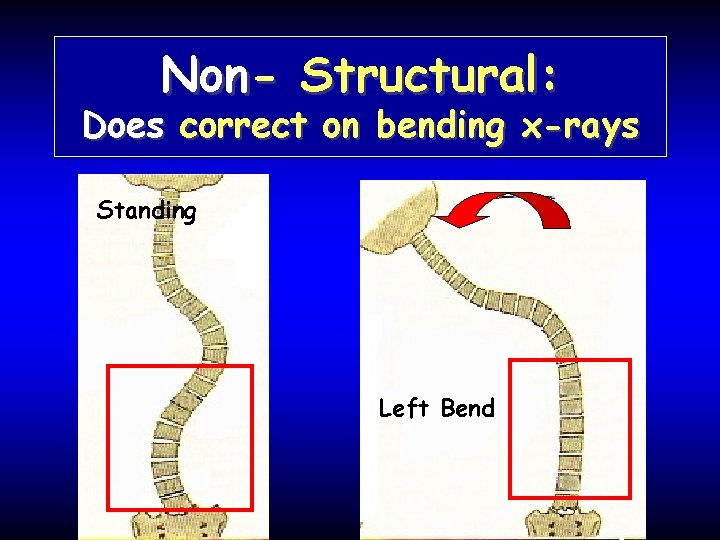

Non- Structural: Does correct on bending x-rays Standing Left Bend

Structural: Does NOT correct on bending x-rays Standing Right Bend